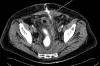

The management of enterocutaneous fistulas continues to be a challenging postoperative complication. Understanding the anatomy of the fistula optimizes its evaluation and management. Diagnostic radiology has always played an important role in this task. The use of plain radiography with contrasted studies and fistulograms is well documented in the earliest investigations of fistulas and they continue to be helpful techniques. The imaging techniques have evolved rapidly over the past 15 years with the introduction of cross-sectional imaging, ultrasound and endoscopy. The purpose of this chapter is to review both the diagnostic and therapeutic roles of fistulograms, small bowel follow-through, computed tomography, magnetic resonance imaging, ultrasound, and endoscopy in the setting of acquired enterocutaneous fistulas.